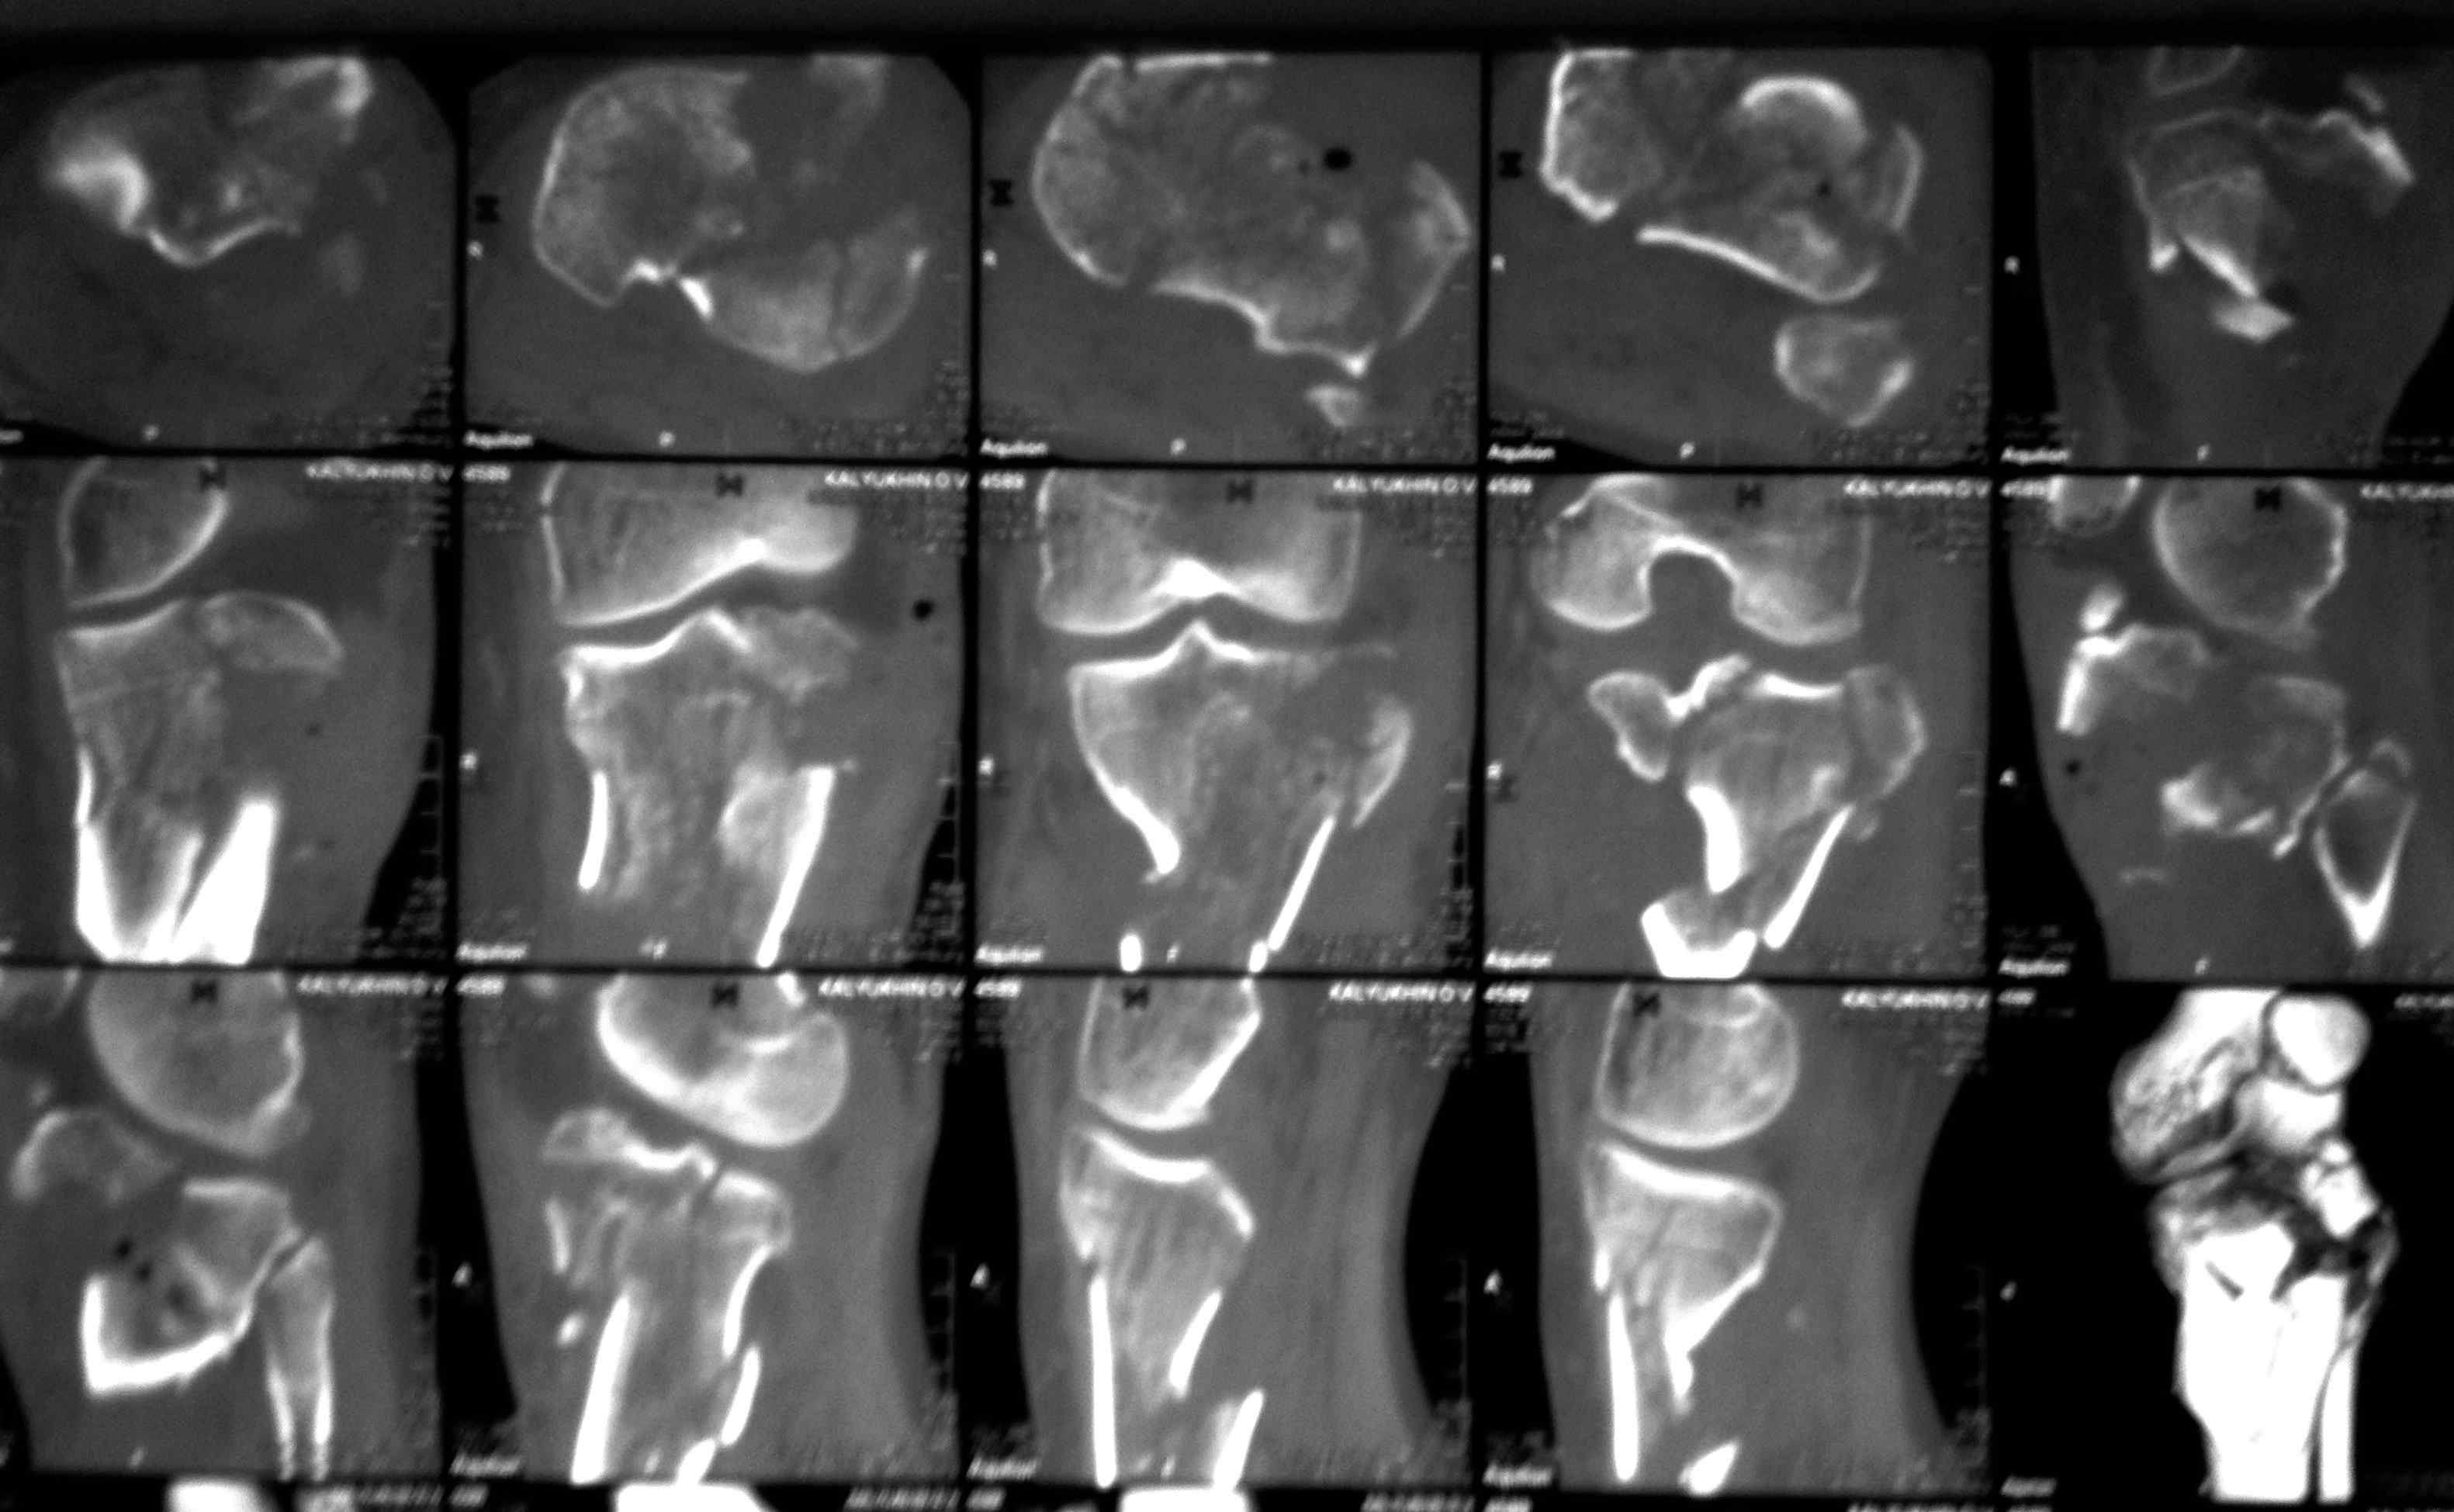

[Ortho] перелом проксимальной тибии + вывих бедра

Высокоэнергетическая травма около недели назад, мужчина 39 лет

По месту поступления вывих бедра вправлен, ПХО раны открытого перелома

б/б кости, скелетное вытяжение. В настоящее время рана заживает неплохо,

небольшое количество серозно-геморрагического отделяемого, состояние

мягких тканей неплохое. Планируем остеосинтез плато из 2-х доступов по

заживлению раны.

1 смущает фрагмент плато в проекции раны, насколько удобно его будет

ловить, попробовать полечить в аппарате + винты

закрыто?